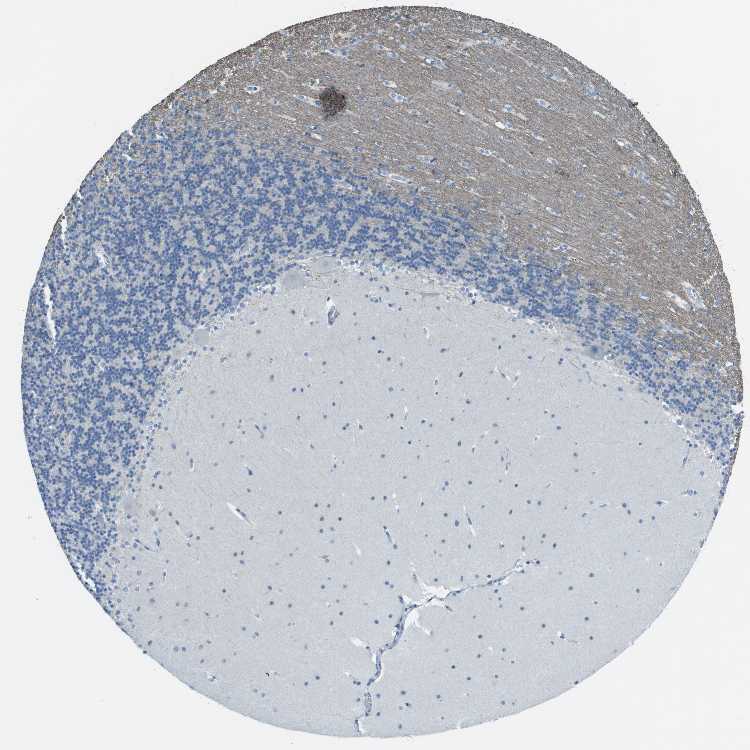

BRAIN CEREBELLUM Show tissue menu

CEREBELLUM - Antibody stainingi

Antibody staining in the annotated cell types in the current human tissue is reported as not detected, low, medium, or high, based on conventional immunohistochemistry profiling in selected tissues. This score is based on the combination of the staining intensity and fraction of stained cells.

Each image is clickable and will lead to virtual microscopy that enables deeper exploration of all samples and also displays staining intensity scores, fraction scores and subcellular localization as well as patient and tissue information for each sample.

Antibody HPA014259

Purkinje cells Not detected

Cells in granular layer Not detected

Cells in molecular layer Not detected